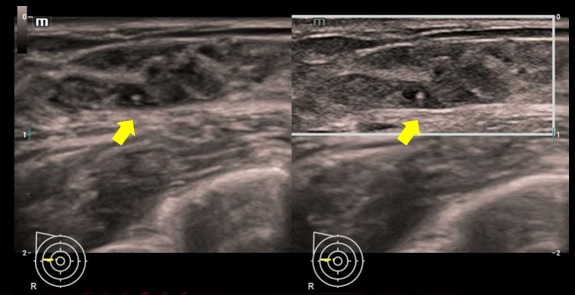

iNeedle - Vylepšenie vizualizácie pomocou ihly iNeedle

iNeedle (kontrastná vizualizácia punkčnej ihly)

iNeedle: Kontrastné zobrazenie bioptickej ihly.

iNeedle: Kontrastné zobrazenie bioptickej ihly.

iNeedle - Vylepšenie vizualizácie pomocou ihly iNeedle